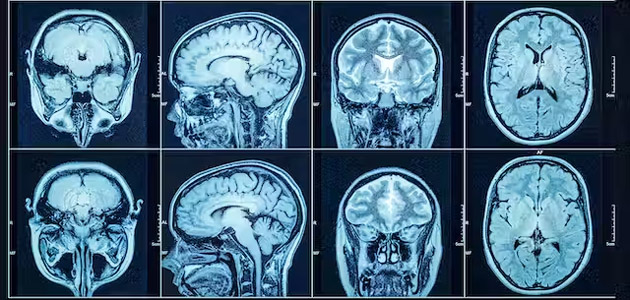

Our latest findings, published in The Lancet Respiratory Medicine, show that nearly a third of people who were severely ill with COVID have multiple organ abnormalities on MRI five months after they were discharged from hospital.

MRI scans revealed that people with long COVID were 14 times more likely to have lung abnormalities than people who never had the disease, three times more likely to have brain abnormalities and two times more likely to have kidney abnormalities.

The extent of MRI abnormalities was linked to the severity of their COVID, their age and whether or not they had other diseases.

People with long COVID who had abnormalities involving more than two organs were four times more likely to report “severe” or “very severe” mental and physical impairment.